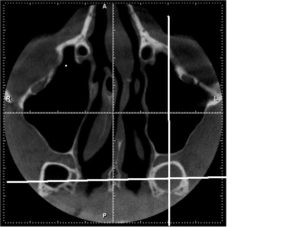

Для диагностики сфеноидита необходимо выполнение Компьютерной томографии (КТ) пазух носа.

Нередко, особенно при хроническом течении, врачи прибегают к проведению компьютерной томографии. С ее помощью удается послойно оценить строение носа и придаточных его пазух. Главное преимущество этого метода – это возможность определить размер соустий, который влияет на частоту рецидивов заболевания и отражается на тактике лечения.

Единственными методами, которые наверняка могут определить сфеноидит, являются компьютерная томография (КТ) или магнитно-резонансная томография (МРТ) –

КТ — исследование пазухи с помощью рентгеновского излучения. КТ позволяет выявить аномалии синуса, степень поражения слизистой. При исследовании с помощью КТ определяется уровень гноя в пазухе.